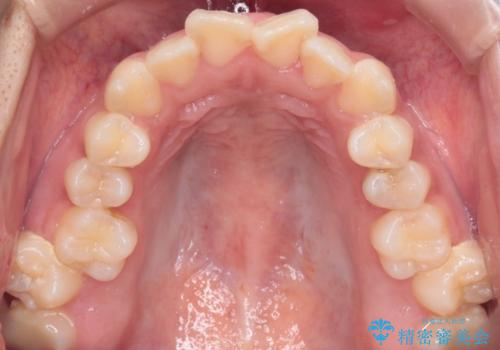

【インビザライン】シザーズバイト、抜歯矯正

- オープンバイトを主訴に来院された患者様です。

抜歯を行うことで、インビザラインを用いて前歯を下げることができ、同時にオープンバイトを改善することができました。

今回はインビザラインのみで治療を終了することができました。